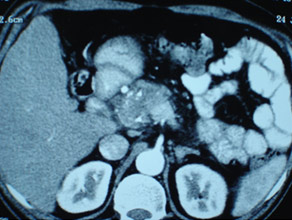

CT scan of pancreatic cancer in the body

Large Neuroendocrine tumour in pancreatic head